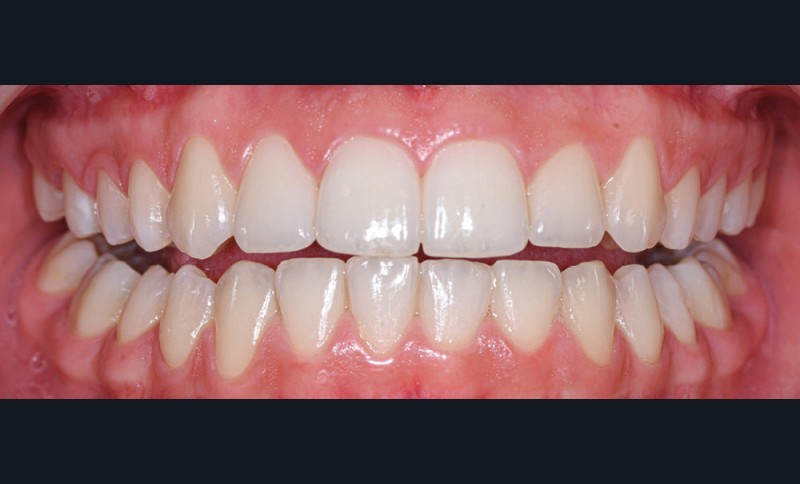

Nous détaillons la technique à travers le cas d’une jeune fille de 18 ans présentant des lésions carieuses sur quatre dents (fig. 1 à 14).